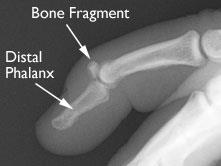

If a fragment of the distal phalanx was pulled away when the tendon ruptured, or if there is some other larger fracture of the bone, it will appear in an X-ray.

Avulsion injury

X-ray shows that a piece of the distal phalanx bone broke away with the tendon.